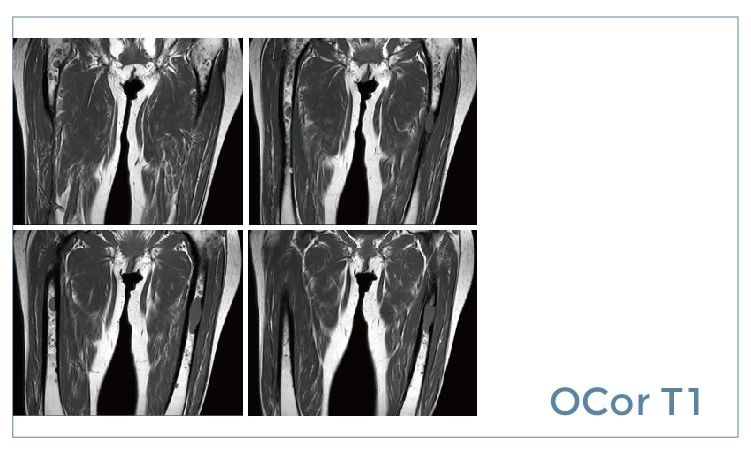

【朗润影像档案】磁共振影像病例分享(编号20190726)